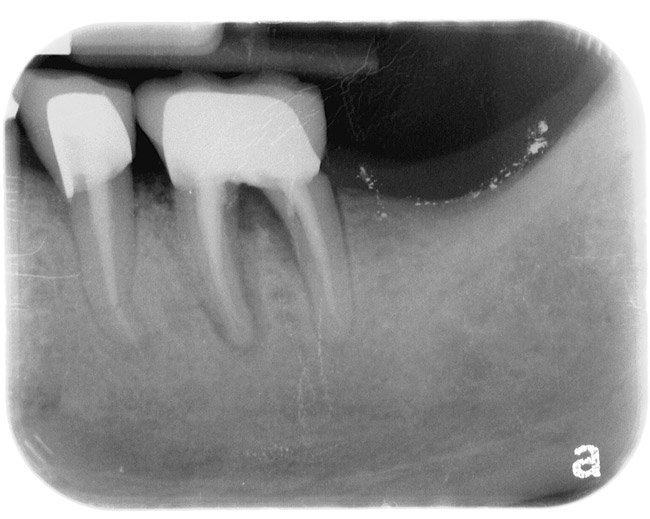

If the tooth has been endodontically treated, the remaining tooth structure relative to the post space needs to be evaluated. The Rule of Thirds is used in this situation. It states that the canal or canal space preparation should not be any wider than one third the mesiodistal root diameter after the endodontic access (Figure 3).3 Once the clinician determines whether adequate tooth structure is present, the second area to evaluate is the distance of the fracture/caries from the crest of bone. To avoid biological width impingement, the minimum distance needed from the osseous crest to the final margin placement is 2.5 mm (Figure 4). As determined in cadaver studies, this consists of approximately 1 mm of connective tissue attachment, 1 mm of junctional epithelium, and 0.5 mm of gingival sulcus.4 This measurement is meant as a guideline and not an absolute number, as it has been shown to have individual variability.5 This actual dimension for the individual patient can be predictably determined by sounding to bone on the adjacent teeth to more closely determine the individual’s biologic width.6

The clinical guideline of 4 mm—consisting of 1.5 mm of tooth structure and 2.5 mm biologic width1,3—is, therefore, the minimum limit for tooth structure above the alveolar bone (Figure 5). If this parameter cannot be met, there are two options for obtaining this threshold. One option is surgical crown lengthening,7,8 and the other is forced orthodontic eruption.9 The choice between each option should be made based on the effect each procedure will have on the esthetics of the case, the crown-to-root ratio, and whether osseous surgery will create a furcation involvement on the adjacent teeth (Figure 6). Esthetic considerations will be addressed later. In terms of crown-to-root ratio, there are two guidelines that exist for determining the minimum ratio (Figure 7). One is the classical 1:1 presented by Penny.10 The second, for maxillary anterior teeth, is 12 mm to 13 mm of tooth with 8 mm to 9 mm of root in bone and 4 mm coronal to the bone, as presented by Spear.1 If all of these criteria for tooth structure are met, then the tooth should be considered an acceptable candidate for retention and restoration. Also, if insufficient tooth structure exists, the required tooth structure can be obtained via forced orthodontic eruption or periodontal surgery provided that the esthetics and periodontal function of the tooth in question and the adjacent dentition are not compromised.